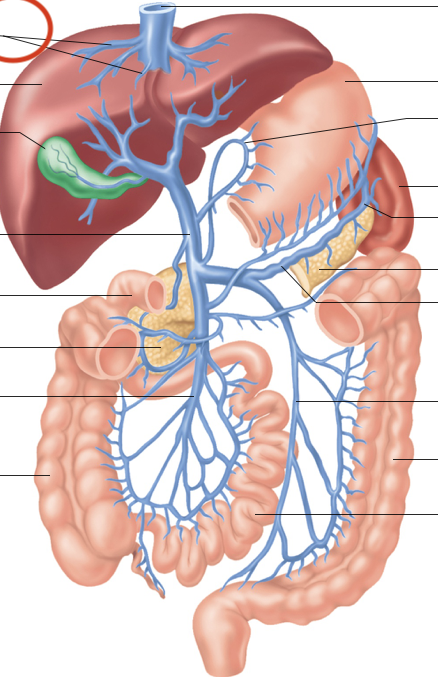

Hepatic Portal System (illustration)

hepatic portal vein

superior mesenteric-small intestine, first half colon

gastric-stomach

splenic-spleen and pancreas

inferior mesenteric-second half colon

hepatic veins